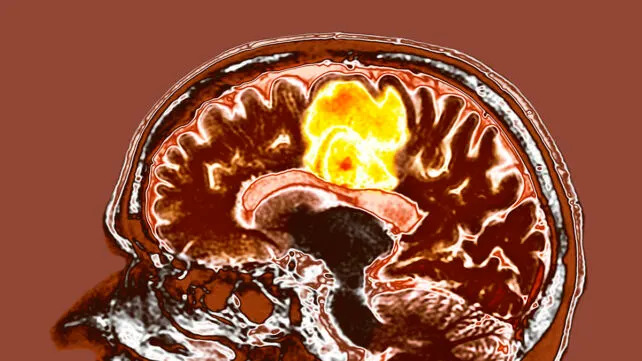

Resveratrol Plus Copper: Experimental Brain Cancer Findings

Researchers testing a simple combination of resveratrol and copper reported modest benefits in treating an aggressive form of brain cancer. The proposed mechanism targets cell-free chromatin particles — fragments of DNA released by dying cancer cells that may inflame and worsen surviving tumour cells. The investigators suggest the supplement pair can reduce these inflammatory fragments and thereby blunt tumour aggressiveness.

Indraneel Mittra, cancer surgeon and public health researcher: "The cell-free chromatin particles... inflame the surviving cancer cells. This makes the disease more aggressive. If you eliminate the cell-free chromatin, which is what the resveratrol-copper tablets do, the cancer is subdued."